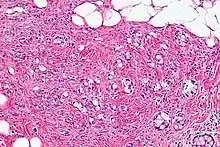

| Micrograph showing a goblet cell carcinoid. H&E stain. | |

Micrograph of a goblet cell carcinoid. H&E stain.

GCCs are diagnosed by pathology. They have a characteristic biphasic appearance which includes (1) goblet cell-like cells, and (2) neuroendocrine-type nuclear chromatin (stippled chromatin).